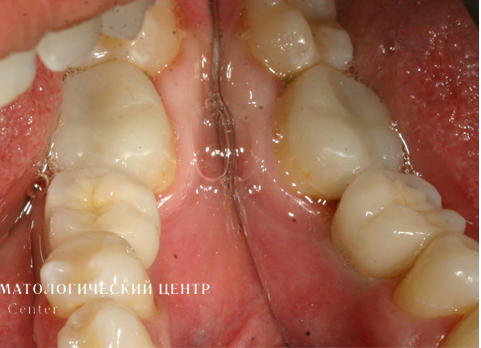

картинка

Этапы лечения

1. Проведена имплантация отсутствующего зуба.

2. Для оптимальной эстетики была изготовлена коронка с каркасом из оксида циркония с использованием индивидуального абатмента, выполненного из аналогичного материала по технологии CAD/CAM. Диоксид циркония (ZrO2) обладает высочайшей степенью биологической совместимости.

Безупречные эстетика и функциональность, полностью воссоздающие соответствующие характеристики естественного зуба. Данный вид ортопедического восстановления не требует специального ухода и не имеет никаких ограничений при пользовании им.

Результат лечения